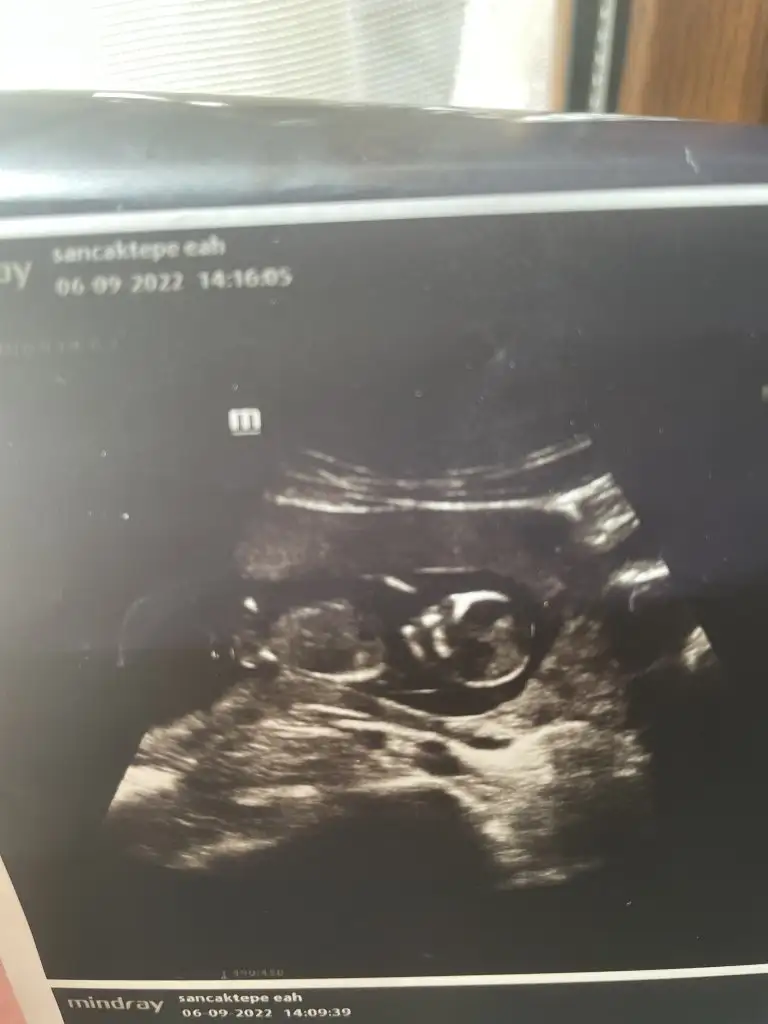

Kız gibi hissettimKızlar iki gün önce 13+2 iken ki us görüntüsü devlet hast ama anlayan var mı nub falanEki Görüntüle 3126510

Hadi bakalımm teşekkürler canımKız gibi hissettimHiçte anlamıyorum Sağlıkla gelsin inşallah